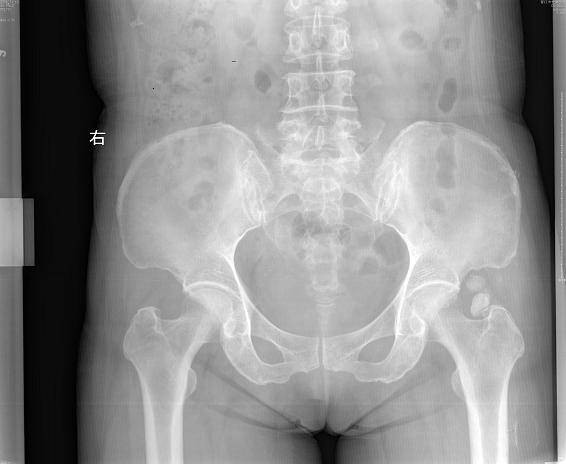

以左髋酸痛半年为主诉来我院就诊

关节腔内游离体,符合滑膜骨软骨瘤

支持:左髋关节滑膜骨软骨瘤。

支持左髋关节滑膜骨软骨瘤病。

滑膜骨软骨瘤,一致通过。